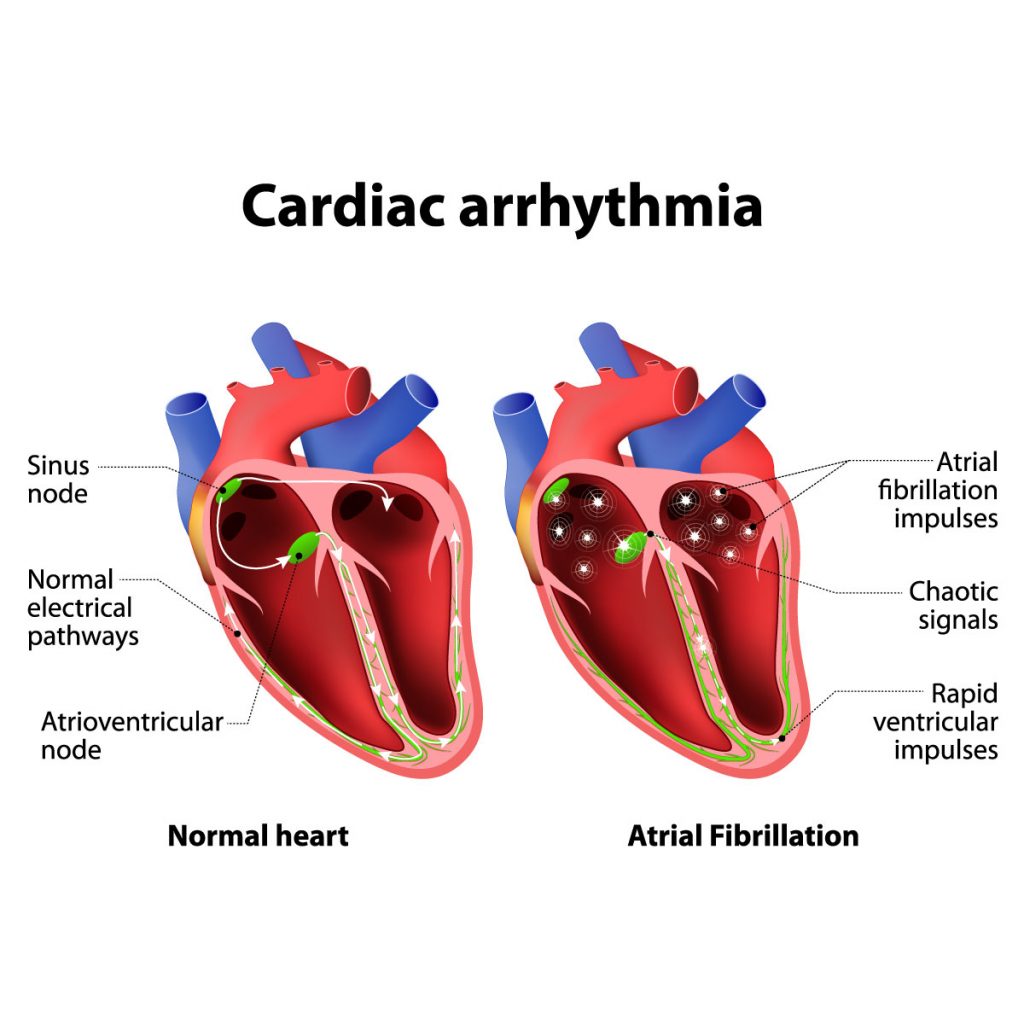

Heart Arrhythmia: Causes, Risk Factors, Symptoms, Treatment

continentalhospitals.comHeart arrhythmia: Causes, Risk Factors, Symptoms, Treatment

continentalhospitals.comHeart arrhythmia: Causes, Risk Factors, Symptoms, Treatment

What Are Arrhythmias And Why Are They Dangerous?: Cardiovascular

www.cardiologytampa.comWhat Are Arrhythmias and Why are they Dangerous?: Cardiovascular …

www.cardiologytampa.comWhat Are Arrhythmias and Why are they Dangerous?: Cardiovascular …

Causes and risk factors of cardiac arrhythmias. New study uncovers major cause of deadly heart arrhythmias. Averting deadly arrhythmias